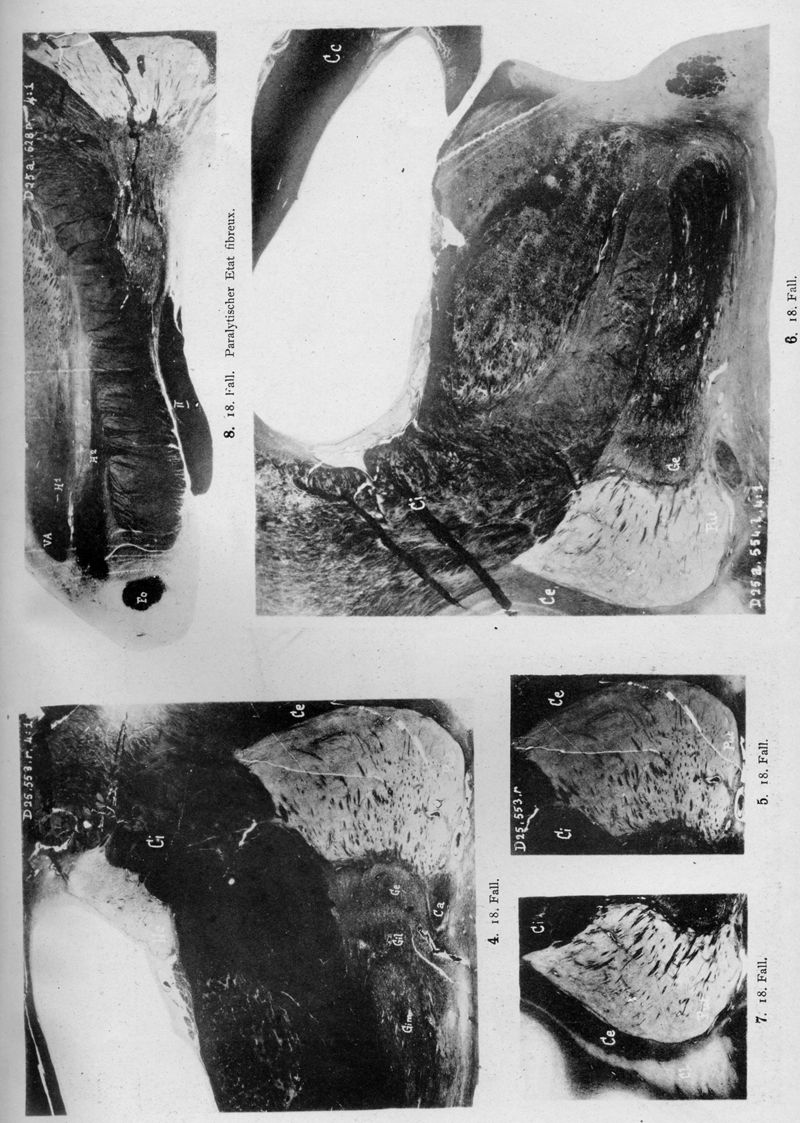

VOGT, Cécile / VOGT, O.

In : Journal für Psychologie und Neurologie,

1920, Vol. 25, pp. 627-846